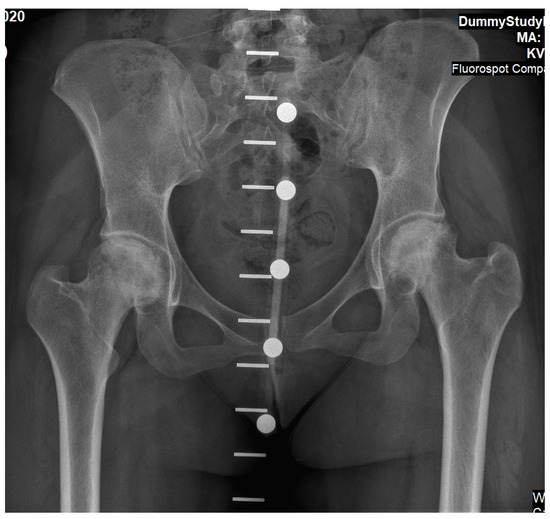

Figure 2.

An antero-posterior X-ray of pelvis and hip joints of Case 1 performed four years after the acute events. These findings present severe bilateral osteoarthritis.